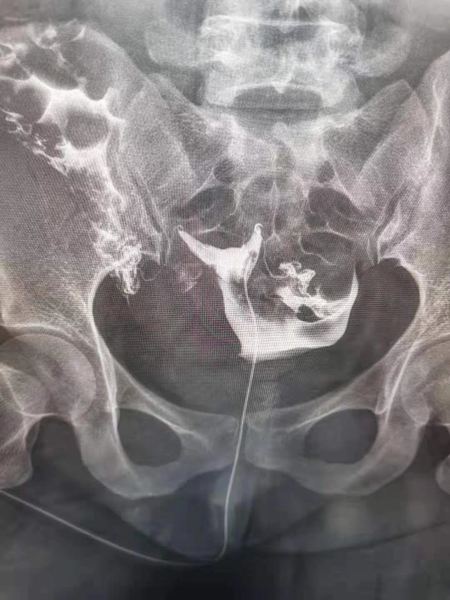

2.診斷同起到治療作用,輸卵管內的炎癥碎片、粘液栓、細小的纖維絲均可引起輸卵管的閉塞,并且輸卵管腔內有復雜的皺襞樣結構,造影劑在通過輸卵管腔時,可通過沖刷疏通的作用,改善輸卵管腔內的粘連堵塞,為精子和卵子的運送提供暢通的道路,還可以恢復腔內纖毛的活動,為運送受精卵做好準備。

3.術后妊娠率高,超液態碘化油或碘水除了有沖刷疏通輸卵管的能力外,還具有改善腹腔環境和內膜狀態的效應,術后妊娠率高。